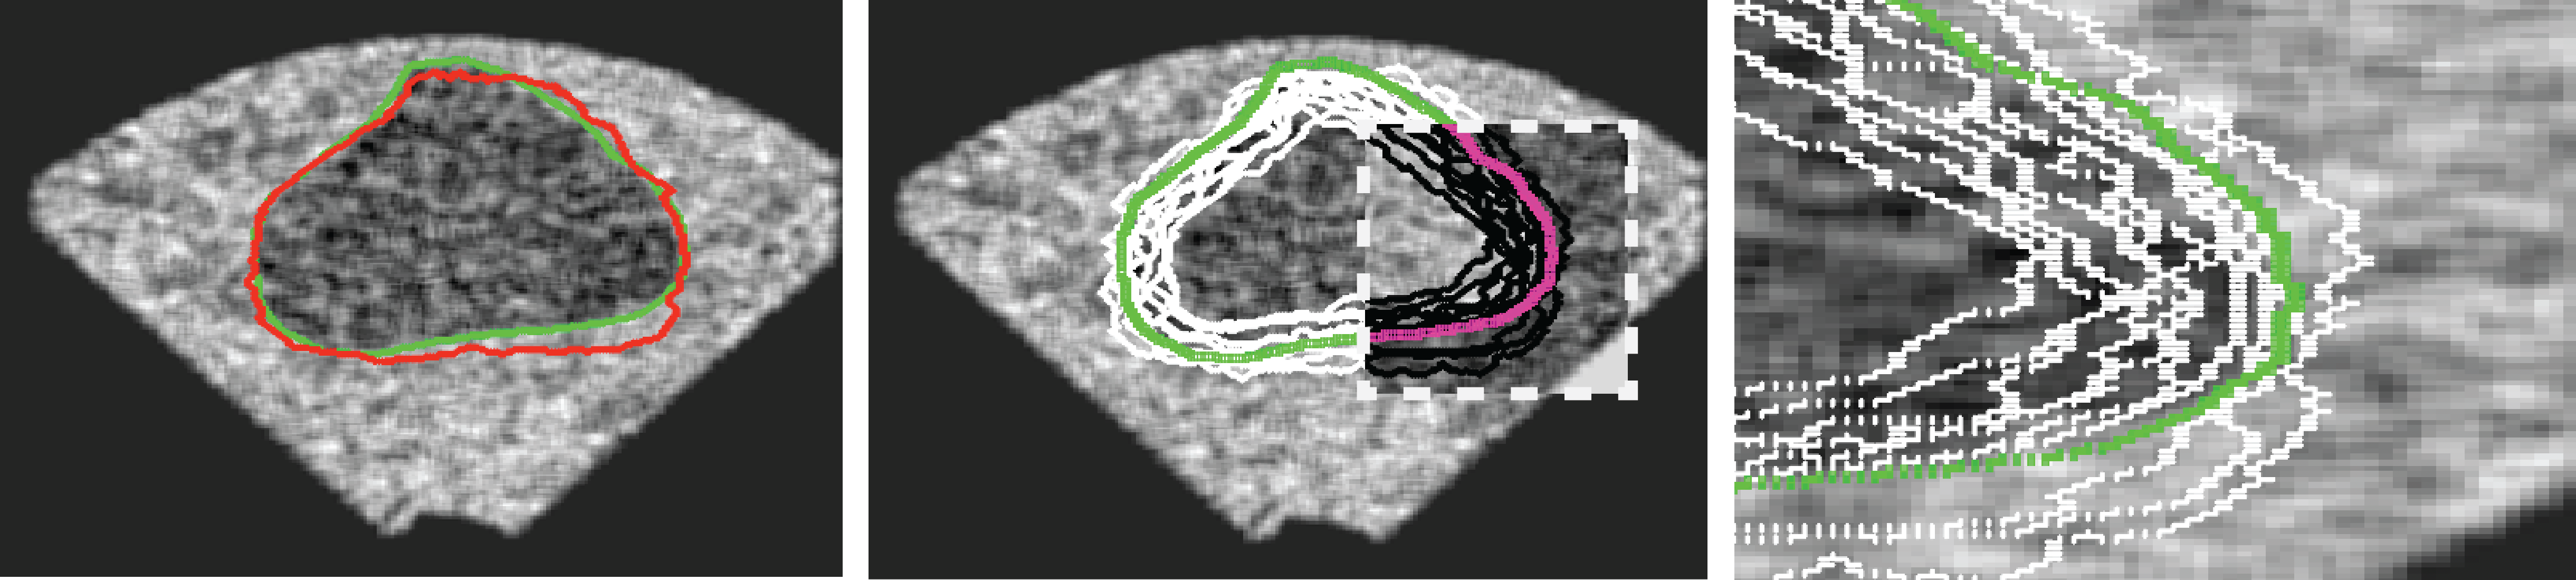

One can show that and , hence . It is obvious that can come from an algorithm in which case is the ground-truth from one or multiple users. As well, can be manual delineation by an expert whereas is then gold standard as consensus among multiple experts. For instance, when segmenting the prostate gland, one has to actually pay more attention to some specific zones such as the rectal wall, neurovascular bundle and urethral sphincter (Figure 2, left). In many cases, a segment may have a large overlap with the ground-truth but may not be accurate enough in significant zones (Fig. 2, right). The accuracy of such segments should be penalized according to the zonal accuracy.

Mapping instead of Registration (Algorithm 3) – Finding the correspondent pixels in and consequently in , given the zonal coordinates in , seems to be a typical “registration” task. However, based on our experimental results we decided to not use registration algorithms for this purpose. The non-rigid registrations we tested were both time-consuming (which may not be a critical drawback) and inaccurate. Whereas one may use a specific registration algorithm in context of a familiar segmentation task, we do provide a quasi-non-rigid mapping procedure that is very fast, due to its simplicity, and can handle small irregularities quite easily. For this, first we do fix some points on the contour of the master gold (see Algorithm 4 in Appendix) and then map them to the ground-truth (see Algorithm 5 in Appendix) and segment (Algorithm 3; see Figure 3).

We generated 500 images from their corresponding gold-standard images111All images and their segments are available online: http://tizhoosh.uwaterloo.ca/. Furthermore, we generated 20 different segments for each image, assuming that there were 20 users. Figure 4 shows five examples of real and synthetic TRUS images. One should bear in mind that the purpose here was not to simulate the images realistically, but rather to have a base from which to generate variable segments from a perfect segment. Figure 5 shows an example of the gold segments and simulated user contours. The variability, coupled with the gold segment, is what is needed in our experiments.